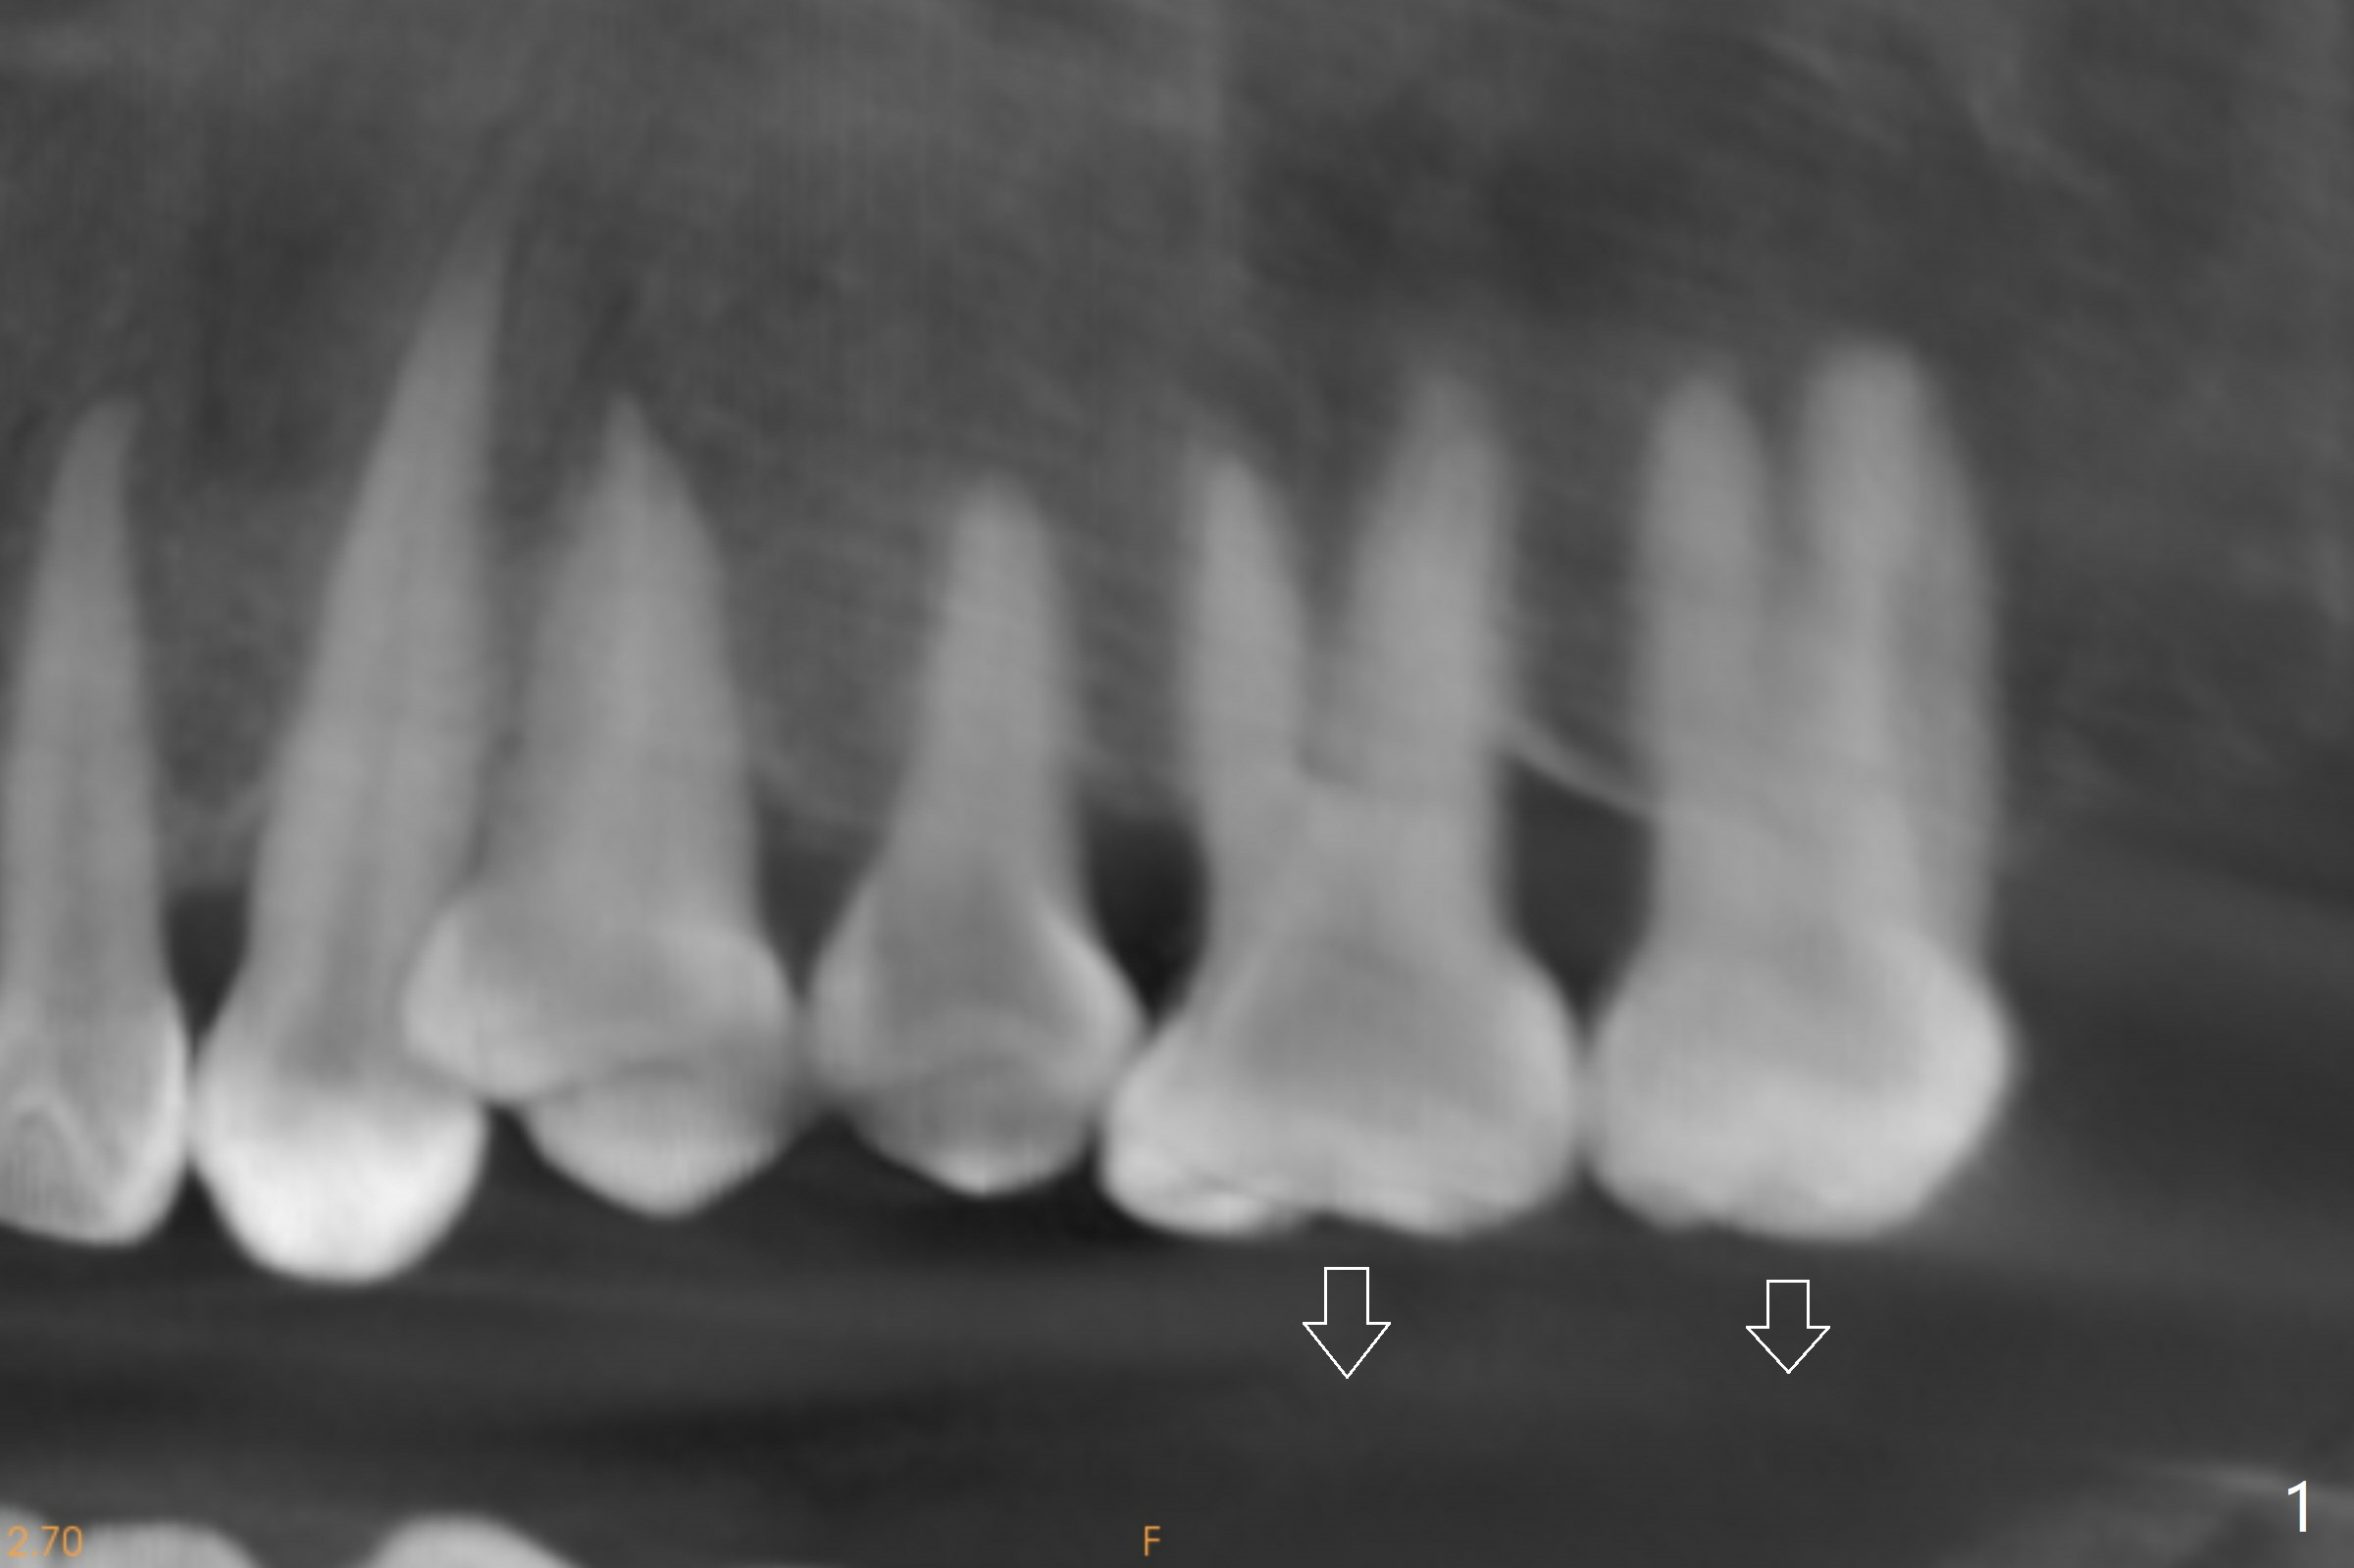

Two months post #19 implant placement, the patient will return to have #14,and 15 supraeruption (Fig.1 arrows) to be taken care of. It appears that there are suitable spaces for mini implants to be placed MP and DB relative to the tooth #14 (Fig.3). Since the palatal (P) mucosa is thicker, a longer mini-implant is expected (8 or 10 mm) palatally, vs. 6 or 8 mm buccally.